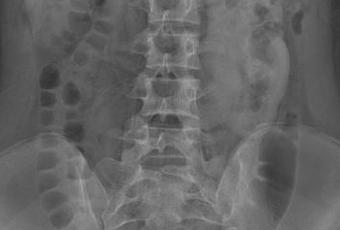

UROGRAFIA EXCRETORA PA POSTERO ANTERIOR

REPORTE DE UROGRAFIA EXCRETORA

Se realiza urografía excretora previa toma de radiografía preliminar. Se obtiene consentimiento informado y se administra de medio de contraste yodado hidrosoluble no iónico y solución fisiológica al 0.9% se toman las proyecciones pertinentes y se observa lo siguiente:

RADIOGRAFIA PRELIMINAR: Se observan piel y tejidos blandos sin lesiones, tejido óseo sin lesiones líticas o blásticas ni perdida de soluciones de continuidad. Órganos intra abdominales y músculos de configuración conservada, patrón de gas con distribución normal, no se aprecian artefactos o tumoraciones evidentes, pelvis sin evidencia de patología.

FASE NEFROGRAFICA: se observan ambos riñones a la izquierda de la línea media del paciente, con adecuada, captación del medio de contraste, observando solo una silueta renal fusionada, con una medida de 157 x 57mm.

FASE EXCRETORA se observa adecuado pase de medio de contraste por sistema pielocalicial, el sistema izquierdo se observa pelvis renal externa, con adecuado paso del medio de contraste en todas las porciones del uréter hasta la unión uretero vesical izquierda. El sistemaa colector derecho (inferior) se observa pelvis bífida, el cual se une a un solo uréter, el cual cruza la línea media a nivel de la porción sacra, para unirse a la unión uretero vesical derecha, mostrándose en todo su trayecto.

La vejiga se encuentra a semirepleción, en su topografía normal, márgenes regulares bin definidos, sin presencia de lesiones.

CONCLUSIONES:

- Ectopia renal cruzada fusionada, con pelvis extrarenal izquierda (superior), pelvis bífida (inferior).

- Unión uretero vesical sin alteraciones.